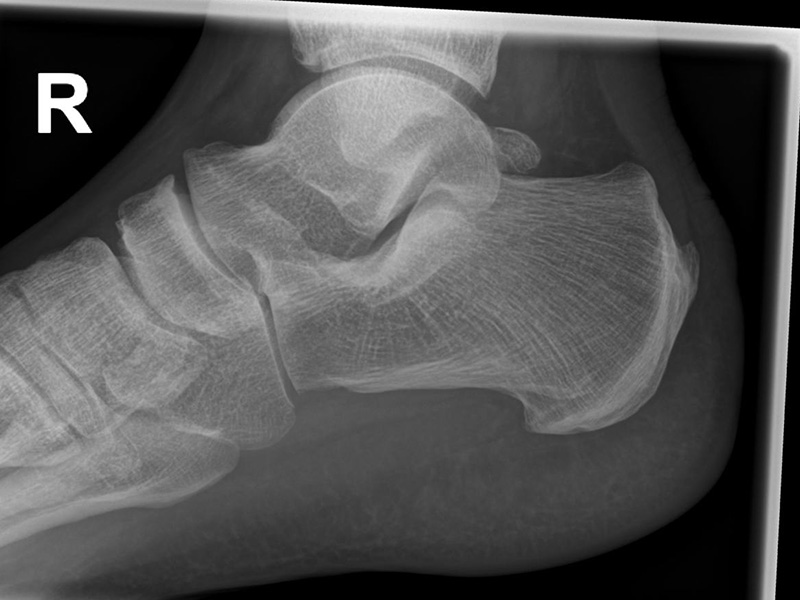

Seitliche Aufnahmen des Sprunggelenks zur Beurteilung der Plantarflexion

Positionierung Variante 1:

• Der Patient steht, beide Beine sind geleichmäßig belastet.

• Der Fuß wird maximal nach ventral geschoben. Zum Ausgleich kann der andere Fuß nach hinten genommen werden. Ziel ist eine Aufnahme in maximaler Plantarflexion des Sprunggelenks.

• Der Zentralstrahl ist in Höhe des Gelenkspalts des OSG auf die dorsale Kante der Fibula zentriert.

• Die Kassette liegt medial dem Fuß an und ist parallel zur Fußachse ausgerichtet.

Positionierung Variante 2:

• Patient liegt auf dem Rücken und dreht den Fuß des aufzunehmenden Beins so nach innen, dass beide Malleolen genau übereinanderstehen.

• Die laterale Fuss-Seite liegt auf der Kassette, das Knie ist leicht gebeugt, das Sprunggelenk maximal plantar flektiert.

• Der Zentralstrahl wird zentral auf das Sprunggelenk gerichtet.

Kennzeichen des Röntgenbildes:

• Tibiagelenkfläche und Talusrolle werden exakt seitlich dargestellt, es kommt zu keinen Doppelkonturen.

• Die Fibula projiziert sich ins mittlere bis hintere Drittel der Tibiagelenkfläche.

• Die vordere und hintere Tibiakante, das Chopart-Gelenk und das Subtalargelenk kommen zur Darstellung. Das proximale Ende des Os metatarsale V ist mit abgebildet. Der Weichteilmantel (Achillessehne) ist erkennbar.

• Die Aufnahme eignet sich insbesondere zum Nachweis eines dorsalen knöchernen Impingements, meist zwischen der dorsalen Tibia und einem prominenten Processus posterius tali.

• Beurteilung des maximalen plantaren Bewegungsausschlags oberen Sprunggelenks.

Besondere Bemerkungen zum Beispielbild:

• Maximale Plantarflexion am unbelasteten Sprunggelenk.

• Dorsal Kontakt des Processus posterius talis mit der dorsalen Tibiakante.